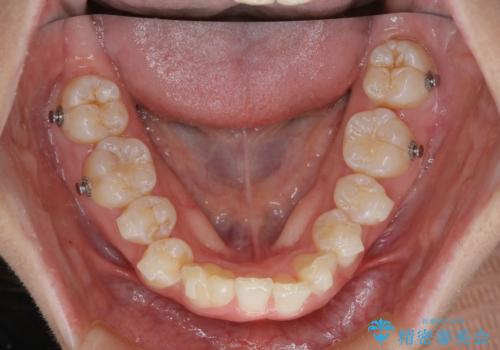

【インビザライン】抜歯矯正

- 前歯のガタガタを主訴に来院されました。

抜歯を行い、インビザラインにて治療を完了しております。